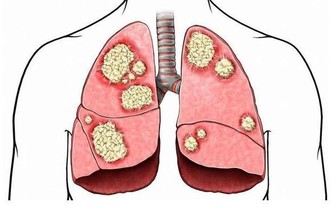

該研究團隊大約蒐集了約48 萬名成年人的健康數據,進行了為期10 年的跟踪調查;

經統計,這些調查對像中包括121 名肝癌患者、100 名膽囊癌患者,以及40 名肝內膽管癌患者。

研究人員檢測了癌症患者的血硒水平,並與健康個體的血液樣本進行對比;

而後發現這肝癌患者的血硒水平都遠低於健康人。

與血硒水平較高的人相比,缺硒的個體罹患肝癌的風險要高出5 到10 倍。